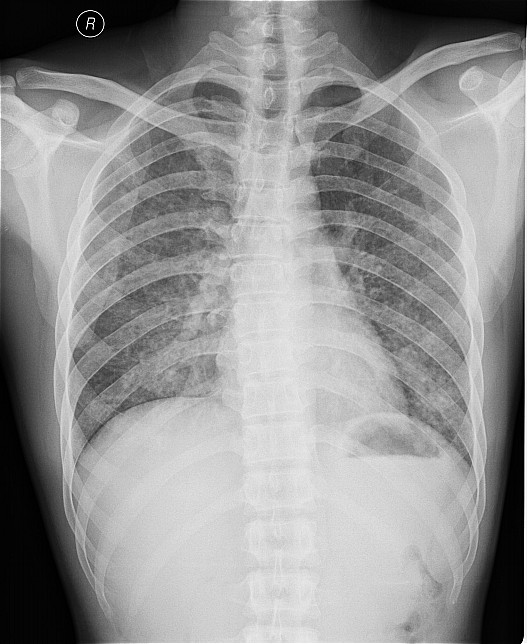

一钨矿工厂因有毒气体泄漏(据说是硝酸)造成十多名工人中毒,均出现不同程度的咳嗽,气逼,心跳加快等中毒症状.其中有几例患者胸片出现小点片状,结节状阴影.是此次中毒引起的肺部改变还是原来就患有矽肺病或其它病变.

肺水肿,及原来就患有矽肺病

原就有的矽肺,未见中毒性肺水肿

矽肺,部分胸片可见肺水肿。治疗复查